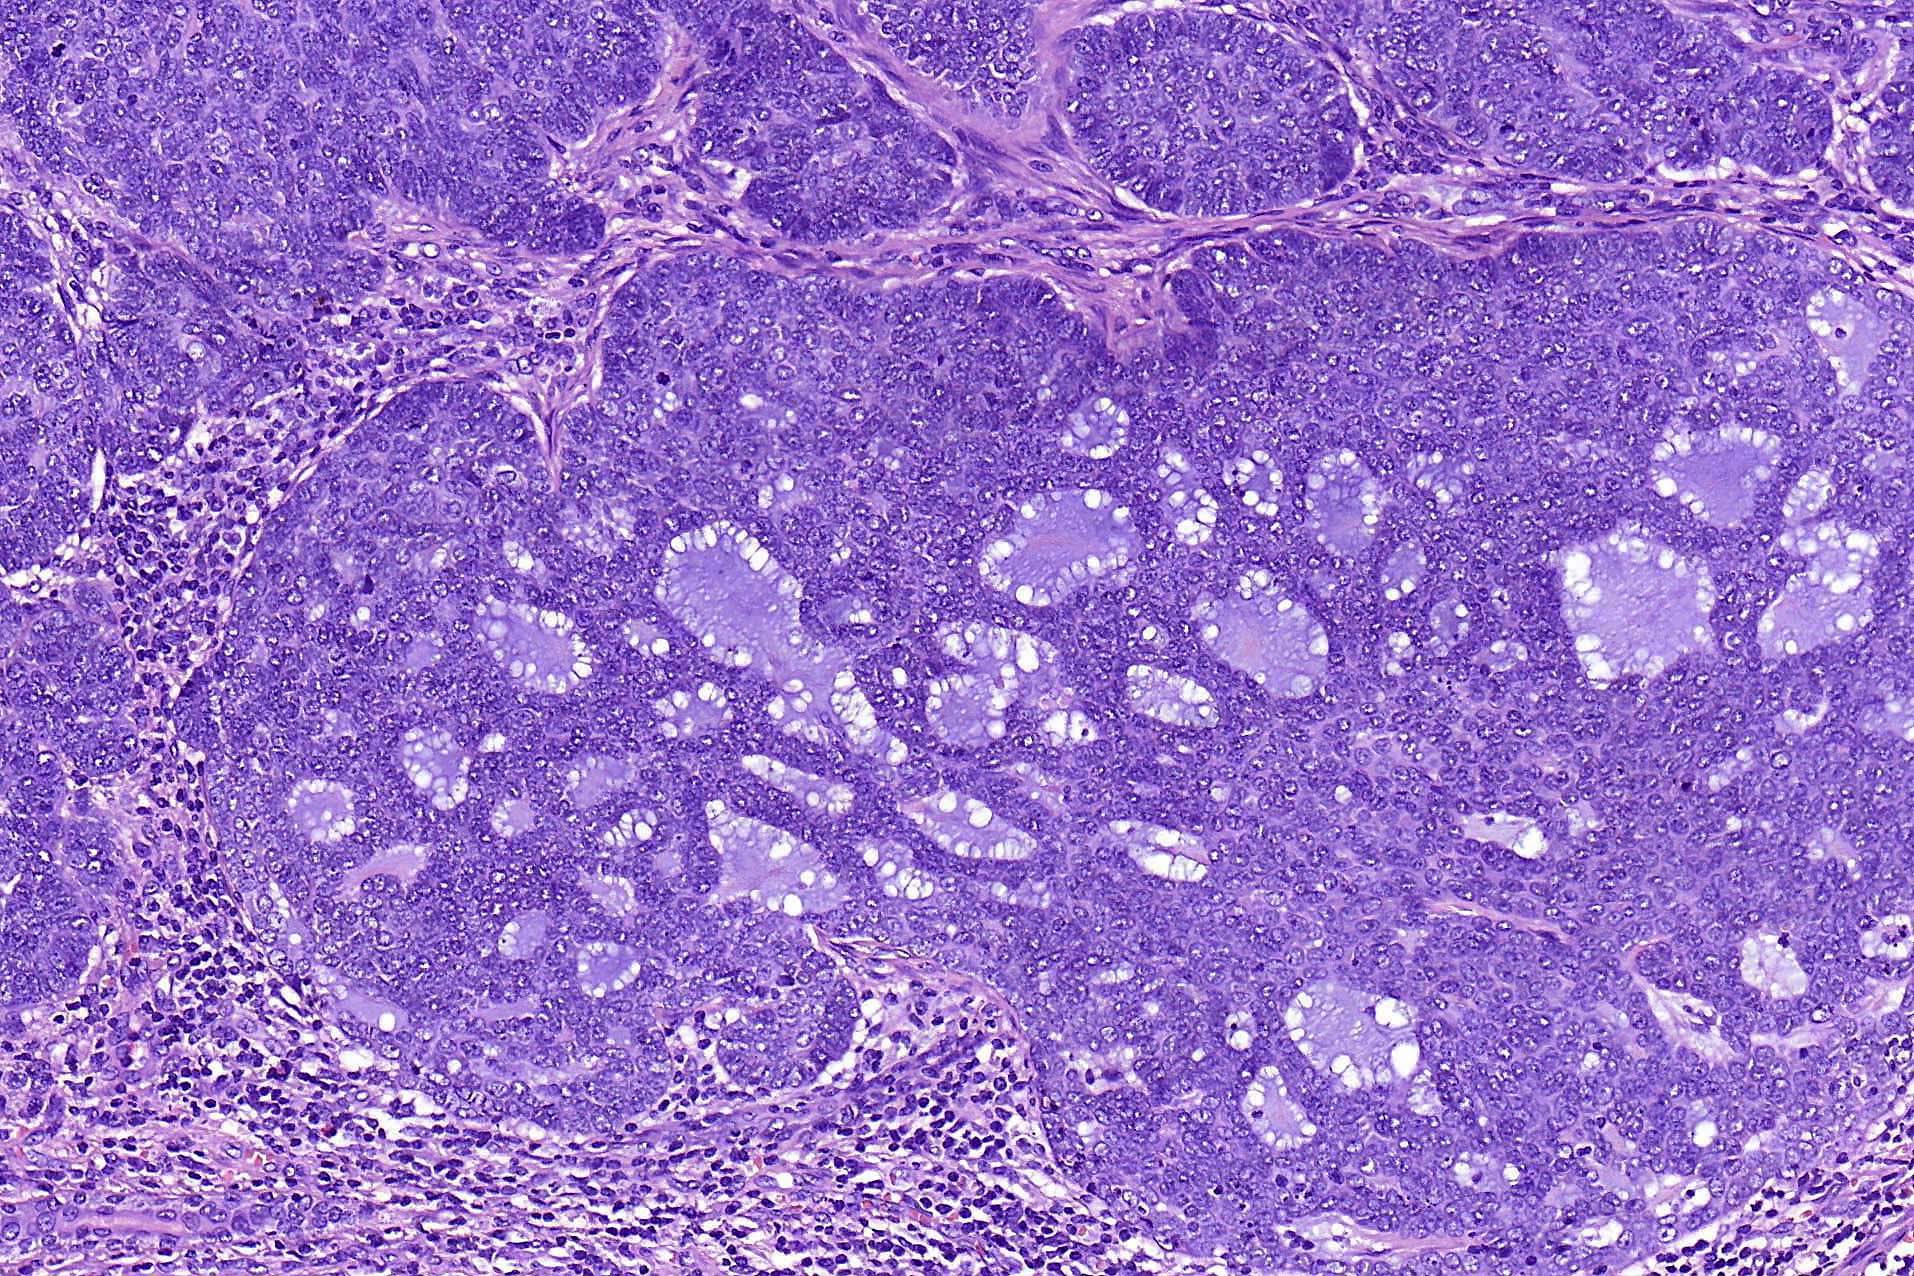

- Adenoid BCC

- Reticulate pseudoglandular pattern of basaloid cells

- Mucinous stroma

- Can mimic true gland formation, resulting in diagnostic confusion with a sweat gland adenocarcinoma, e.g. adenoid cystic carcinoma

- Adenoid cystic carcinoma versus adenoid BCC:

- Well defined cribriform patterns

- No peripheral palisading, continuity with the epidermis or adjacent hair follicle or retraction artifacts between the tumor islands and stroma

- Typically shows hyaline material lining the lumina of the ducts and sometimes also present in the stroma

- CD117+ (20% of BCC CD117+), CD43+ (40%), CK7+, CEA+, EMA+ (in ductal structures)

- p63+, SMA+, calponin+ (myoepithelial cell population at periphery of tumor islands)

Microscopic (histologic) images

Contributed by Antonina Kalmykova, M.D., Phillip H. McKee, M.D., Sate Hamza, M.D., Eduardo Calonje, M.D.,

Wayne Grayson, M.B.Ch.B., Ph.D., James Sampson, M.B.B.S., M.Sc. and Assia Bassarova, M.D., Ph.D.